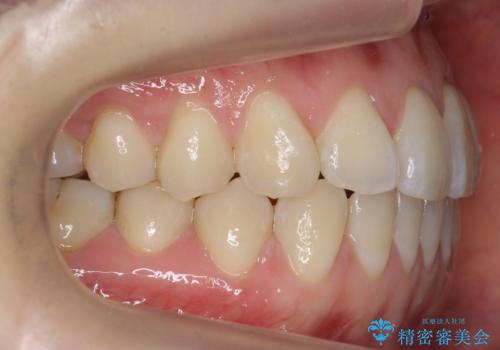

前歯が気になる 大人のマウスピース矯正 矮小歯を整える

- 前歯の並びを主訴に来院。

マウスピースで歯を抜かずに治療しています。

左上の前歯が飛び出しており、唇が笑った時に引っかかっていたのが解消しています。

左上の前歯は小さいため、(矮小歯)左右対称になるようにセラミックで形を修正する治療も併用しています。

歯を大きくかぶせるスペースを作るため、右上の奥歯を後ろに下げています。

左にずれていた上の正中も揃い、大変喜んでいただきました。